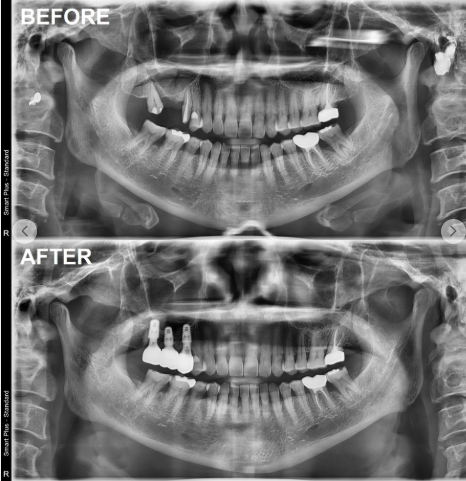

비슷한 연령대의 치료 사례를 확인하세요.

"우리 어머니 나이 또래 환자를 많이 치료해 본 곳인가?"

이런 사례들을 보면 병원의 어르신 임플란트 경험을 가늠할 수 있습니다.